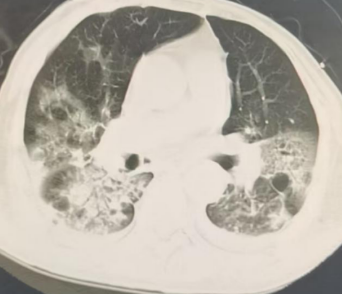

2025-10-22胸部CT:气管插管术后,气管腔内可见高密度影附着。桶状胸廓,双肺可见多发类圆形无壁及薄壁透光区,双肺内可见散在斑片状稍高密度影,边缘模糊不清,部分实变。双侧胸腔内可见弧形液体密度影。主动脉及冠状动脉走行区可见致密影。双侧胸腔内未见积液。